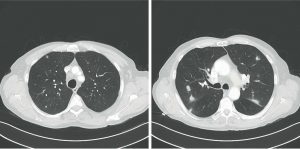

Une pneumopathie atypique typique…

Nous rapportons le cas de M.C., 75 ans, asthmatique depuis ses 17 ans et suivi pour une maladie de Crohn diagnostiquée en 1997 sans traitement spécifique depuis 5 ans. Ancien…